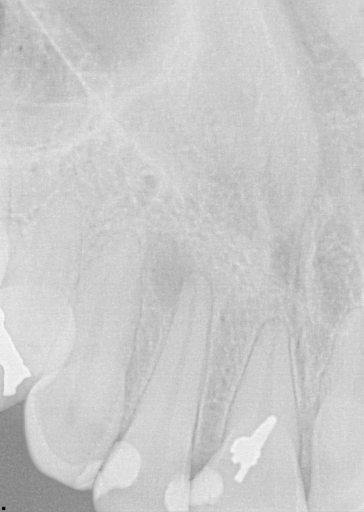

Recently in your practice, it’s very likely that you have: efficiently temporized a broken tooth and reassured a patient that it will be just fine; started endodontic therapy for a patient in acute pain and helped her sleep again; and placed composite on a chipped or broken front tooth and helped the patient smile again. (Figs. 1–3)